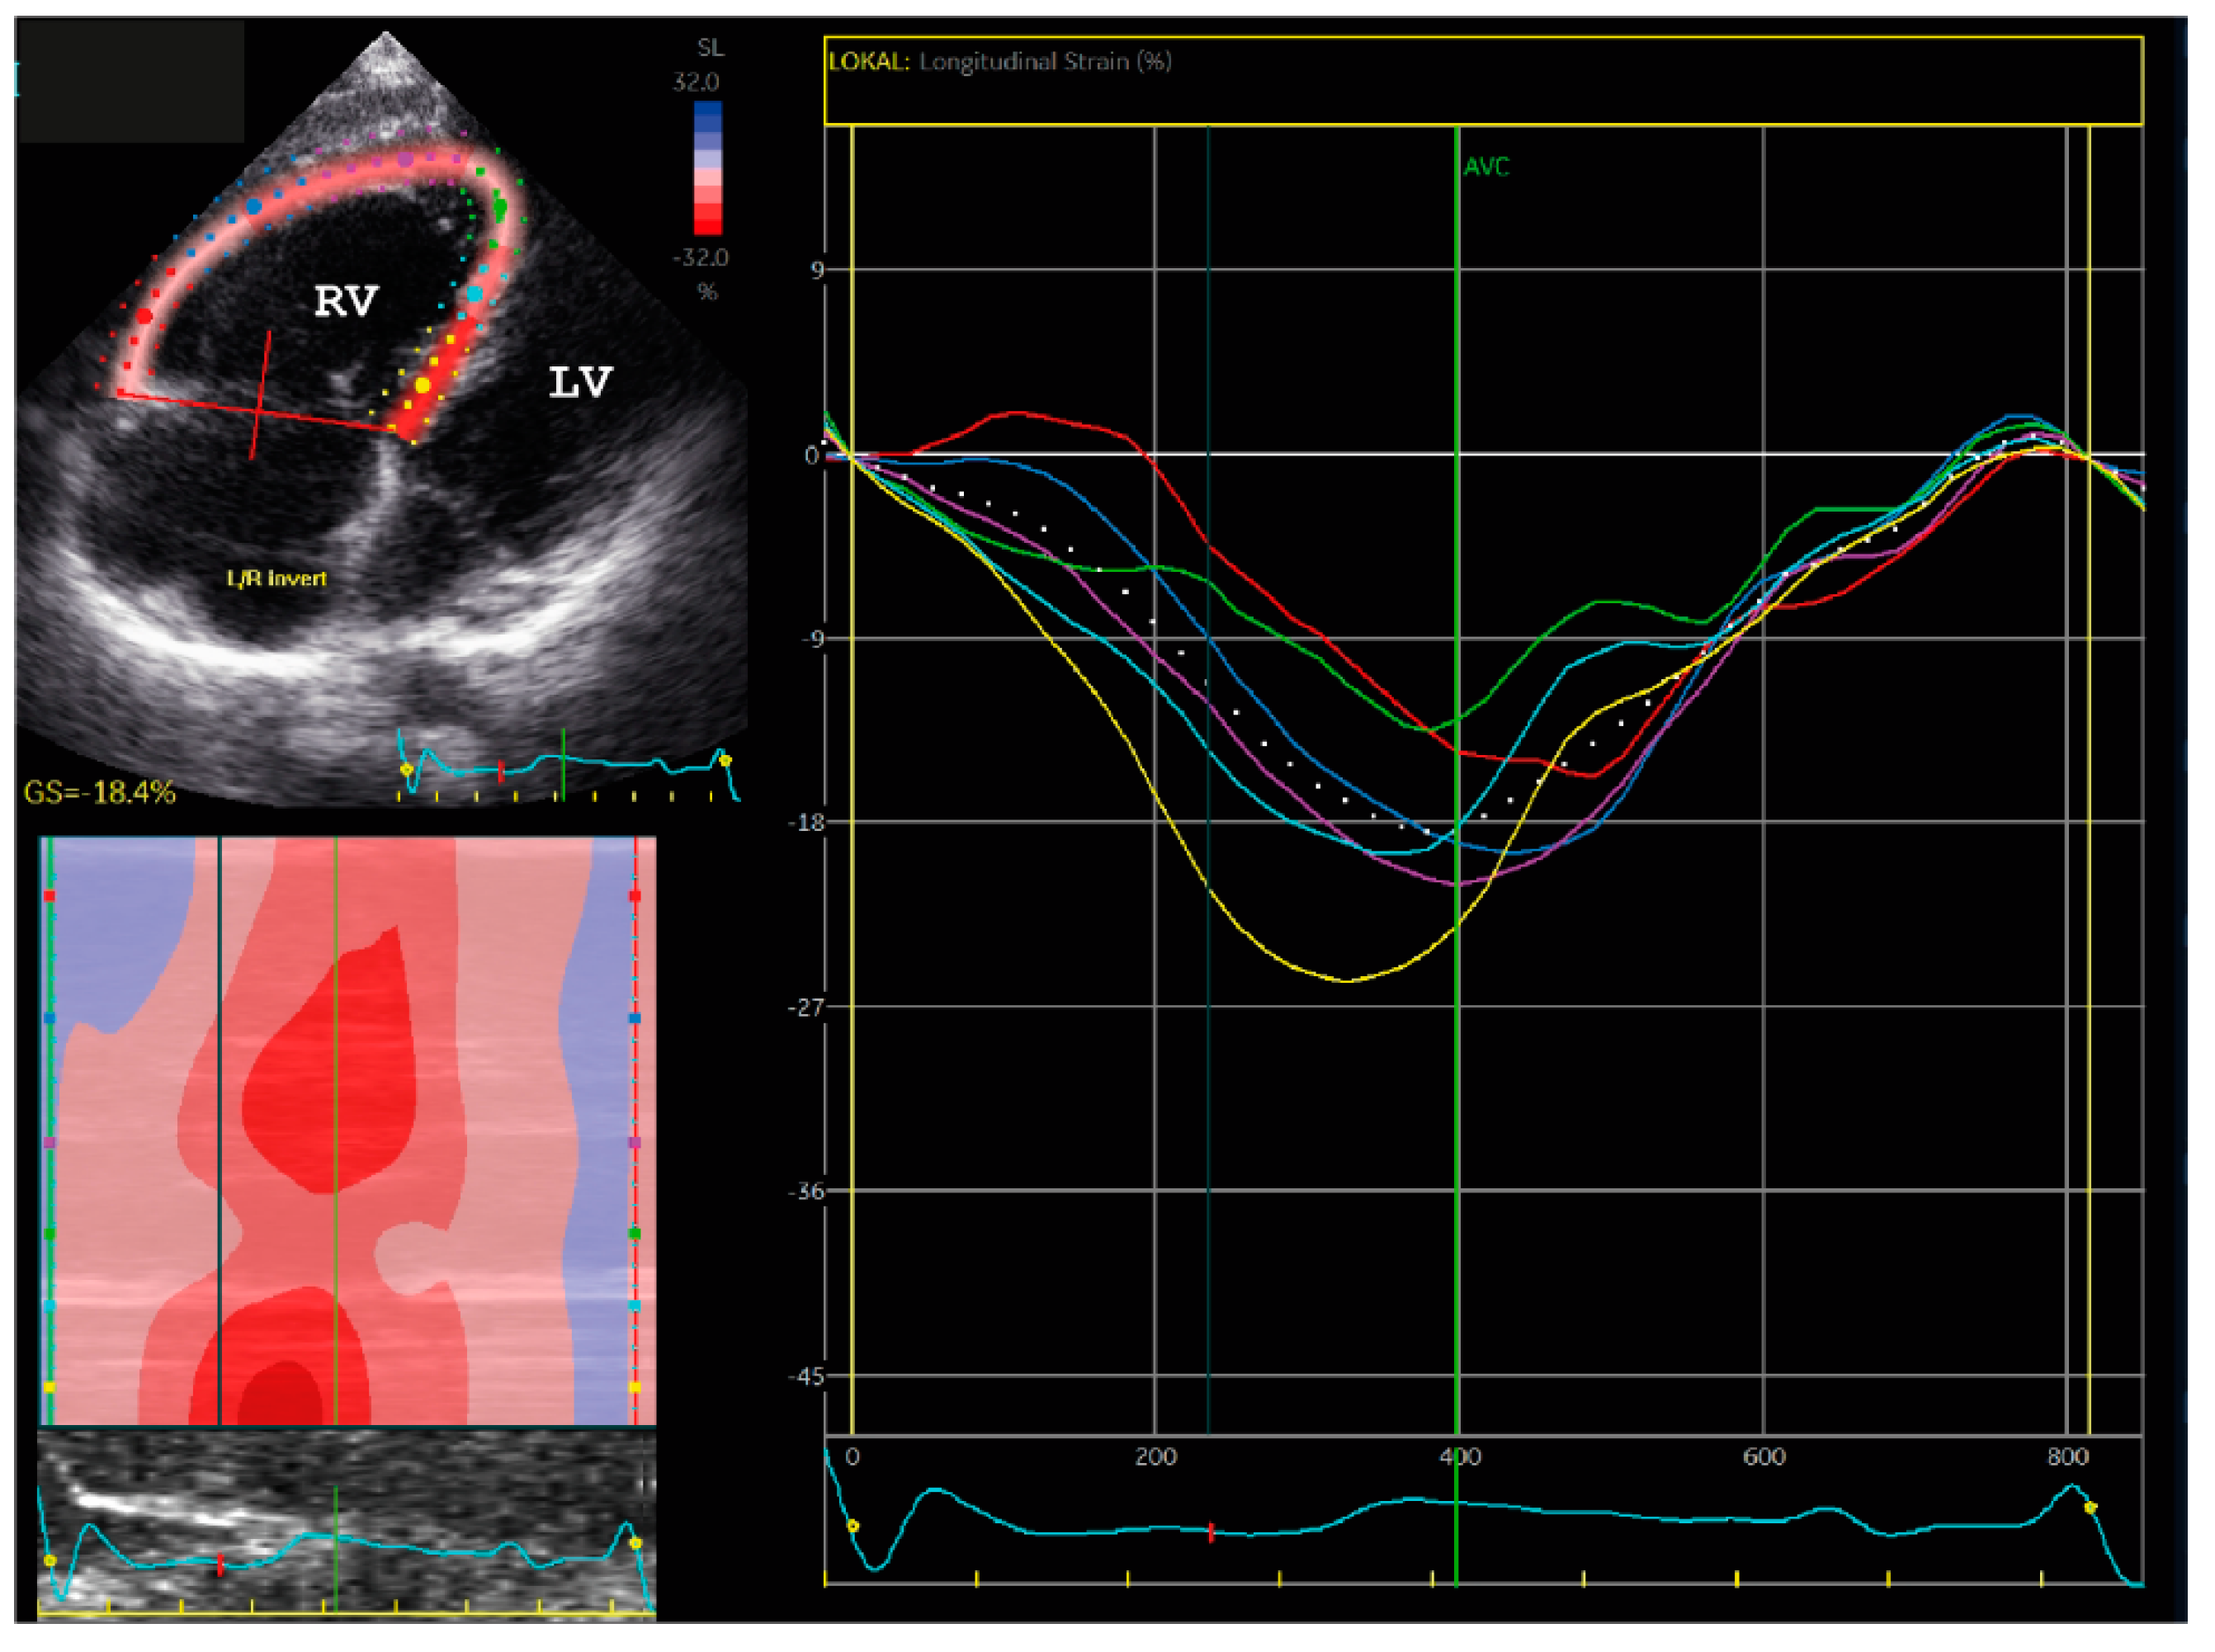

2.1.1. Family A